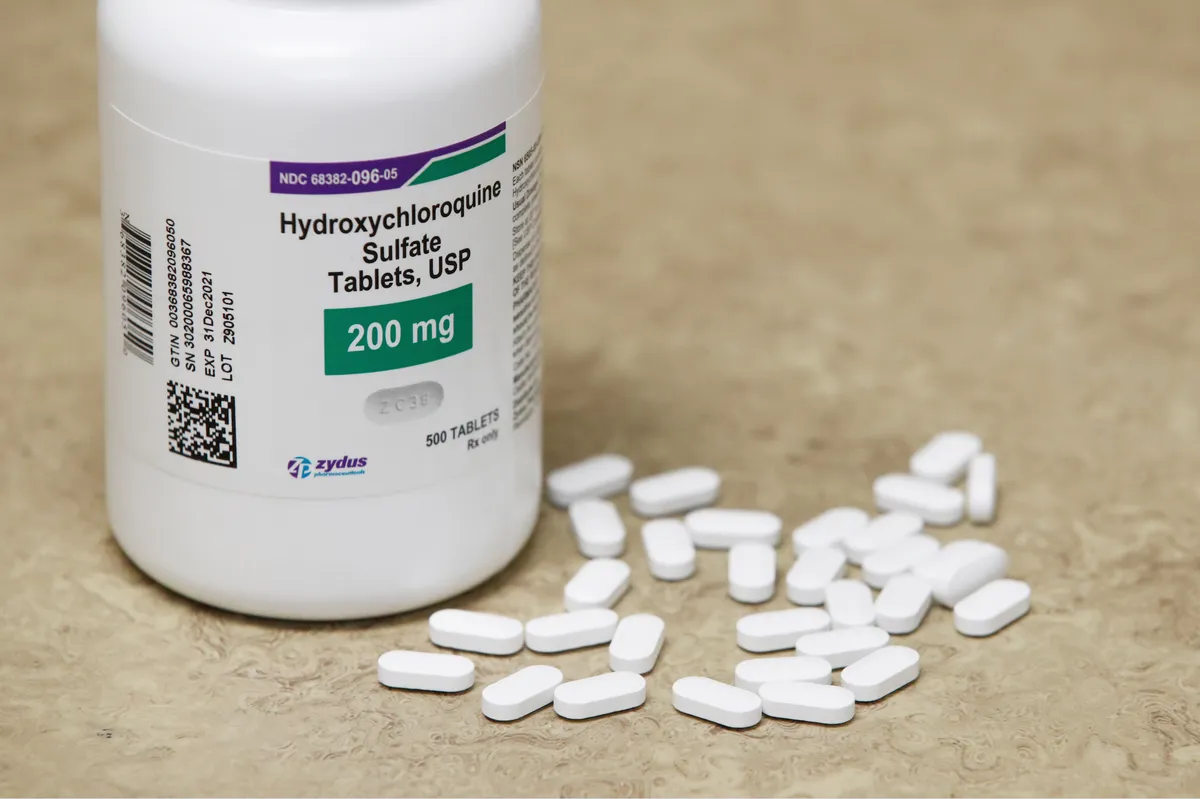

Hidroxicloroquina na IgA gestacional: evidência promissora? Dois casos clínicos recentes mostram melhora da proteinúria com o uso de HCQ em pacientes com NIgA durante a gestação. Uma alternativa segura quando iSRA e SGLT2i estão contraindicados. Vale a pena conhecer!

Valkercyo Feitosa

12 meses atrás